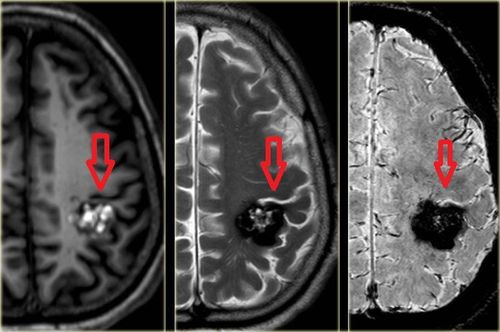

U máu thùy trán phải kiêng những gì?

Chào bác sĩ! Thưa bác sĩ, em bị u máu thùy trán phải. Bác sĩ cho em hỏi, em bị u máu thùy trán phải kiêng những gì ạ? Cảm ơn bác sĩ!